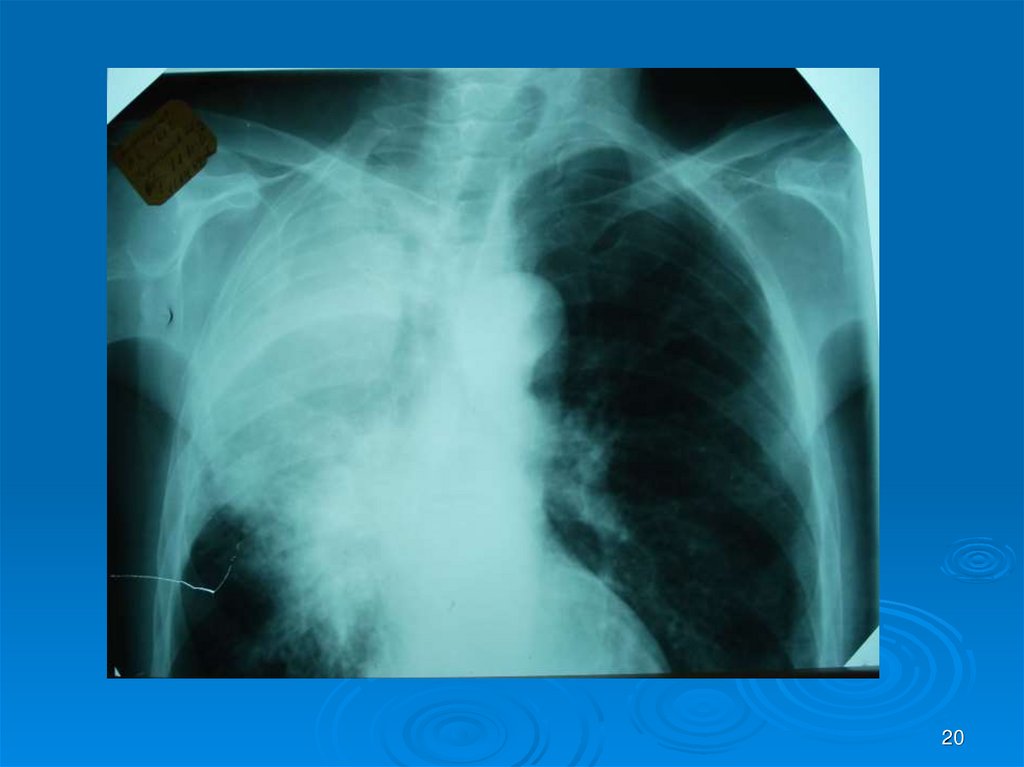

Каждый из вас должен интерпретировать Rснимки (всего 30) в ММ-презентации: назвать

заболевание, его локализацию, если осложнение

заболеваний – то указать какое. На снимках могут

быть пневмония (очаговая, сегментарная,

долевая), абсцесс легких I и II стадии, гангрена

легких, плеврит, ХОБЛ и сходные с ними болезни

легких, требующие дифференциальной

диагностики (туберкулез и др.). Успехов в работе!

20.

20